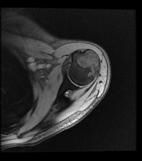

Kondroblastom

Uzun kemiklerin uç kısmından (epifiz ve apofiz bölgelerinden) kaynaklanan, kıkırdak üreten ve selim (iyi huylu) tümördür. Genellikle ergenlik döneminde rastlanır. En sık rastlandığı bölgeler kol kemiğinin (humerusun) üst kısmı ve diz civarıdır. Bulgular komşu eklemde hafif şişme ve rahatsız edici ağrıdır. Uygun tedavi lezyon içerisine girerek küretaj (kazıma), sonra kriyoterapi veya kimyasal koterizasyon uygulanmasıdır. Kavite (boşluk) temizlendikten sonra greftleme yapılır. Agresif lezyonlardagreftleme yerine kemik çimentosu uygulanabilir. Ameliyat öncesi yapılacak embolizasyon kanama miktarını azaltır. Ameliyat sonrası dönemde 3’er aylık aralarla kontrol yapılmalıdır. Kötü huylu tümöre dönüşü oldukça nadirdir.